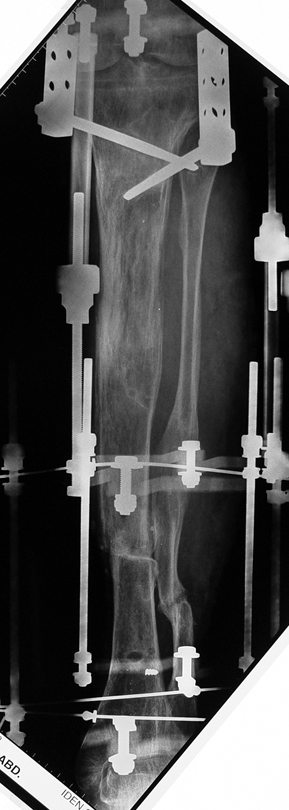

Appropriate radical debridement necessitates excision of all necrotic bone and soft tissues, and frequently causes instability at the involved extremity. The remaining bone and soft tissue defect has to be fixed and reconstructed. The distraction osteogenesis method of Ilizarov is used successfully for achievement of union, correction of the deformity, elimination of limb length inequality and reconstruction of segmental bone defects.

The duration of external fixation (external fixation index) depends on the amount of distraction required, and the extremity is prone to complications during this period. After the distraction phase is completed, the external fixator remains in place during the consolidation phase, which lasts twice as long as the distraction phase; but this period is hardly tolerated. If the external fixator is removed before sufficient consolidation is achieved, fractures, deformity and shortness will be the result. In our department, ‘lenghthening over nail’ method is used in order to decrease the external fixation index and increase patient comfort and activity level. In this method, the intramedullary nail is statically locked after the completion of the distraction phase, and external fixator is removed. The extremity is stabilized by the intramedullary nail during consolidation phase. In this way, complications due to long external fixation index or early removal of the external fixator are avoided.